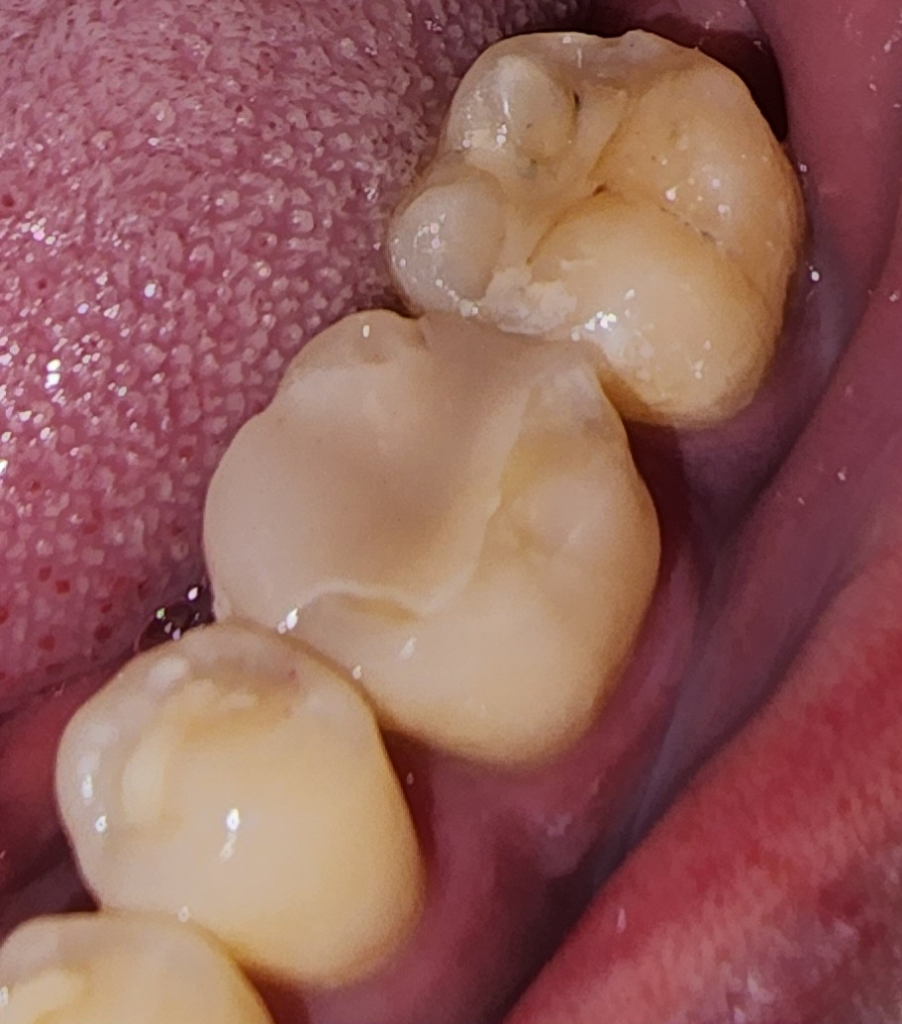

몇일전에 인레이치료 받았는데 마감이...(사진주의)

네이버 인레이한거 사진보면 아주 깔끔하게들 하셨던데. 저는 단차가 있는거 같고 좀지저분한게 된거 같아 문의드려요

이정도면 잘된건가요?

• 1번 째 사진

현재 보여주신 사진은 인레이라기 보다는 온레이에 가깝다고 보시면 됩니다. 즉 단순히 교합면(씹는면)이 아니라 치아의 다른 외형까지 손상되어 한 것으로 보여집니다. 아마 색상 차이로 인하여 훨씬 지금과 같은 생각이 드실 수 있는데 단차가 난다면 다시 해야 하는 것이 맞습니다. 즉 치과 기구로 긁었을 때 자연치와 해당 온레이에 긁히거나 턱이 진다면 다시 제작해야 합니다.

사진상으로 보면 인레이 와 치아공간이잇어 보이긴합니다. 치과에 가셔서 다시한번 체크를 받아보시는게 좋을것같습니다.